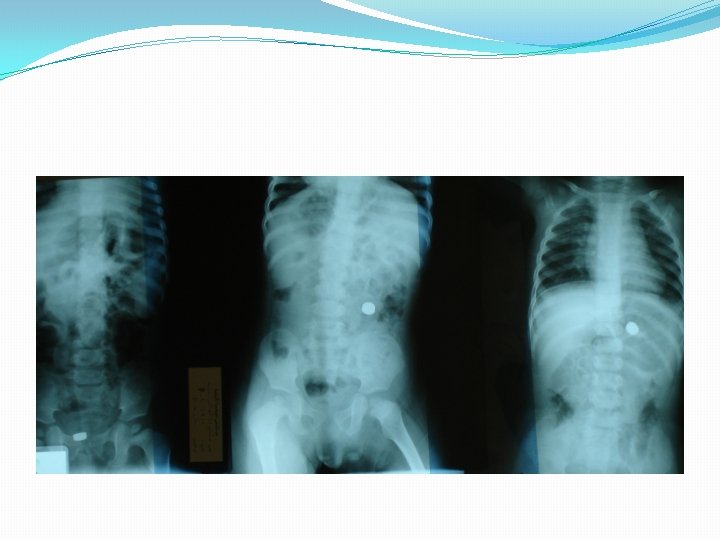

Radiographic examination �consists of anteroposterior and lateral views of the extended neck and chest. � 56% of patients will have a normal chest radiograph �CXR findings: �air trapping : the most common sign �atelectasis �mediastinal shift �Pneumonia �a radiopaque object

Radiographic Findings in Patients With Foreign Body Aspiration Child Group, No. of Radiographs With Diagnosis (% Relative Frequency) Adult Group, No. of Radiographs With Diagnosis (% Relative Frequency) Atelectasis 11 (14%) 9 (50%) Air trapping 49 (64%) 3 (17%) Pneumonia 10 (13%) 3 (17%) 3 (4%) 2 (11%) 9 (12%) 2 (11%) Visible foreign body Normal radiograph

Air trapping